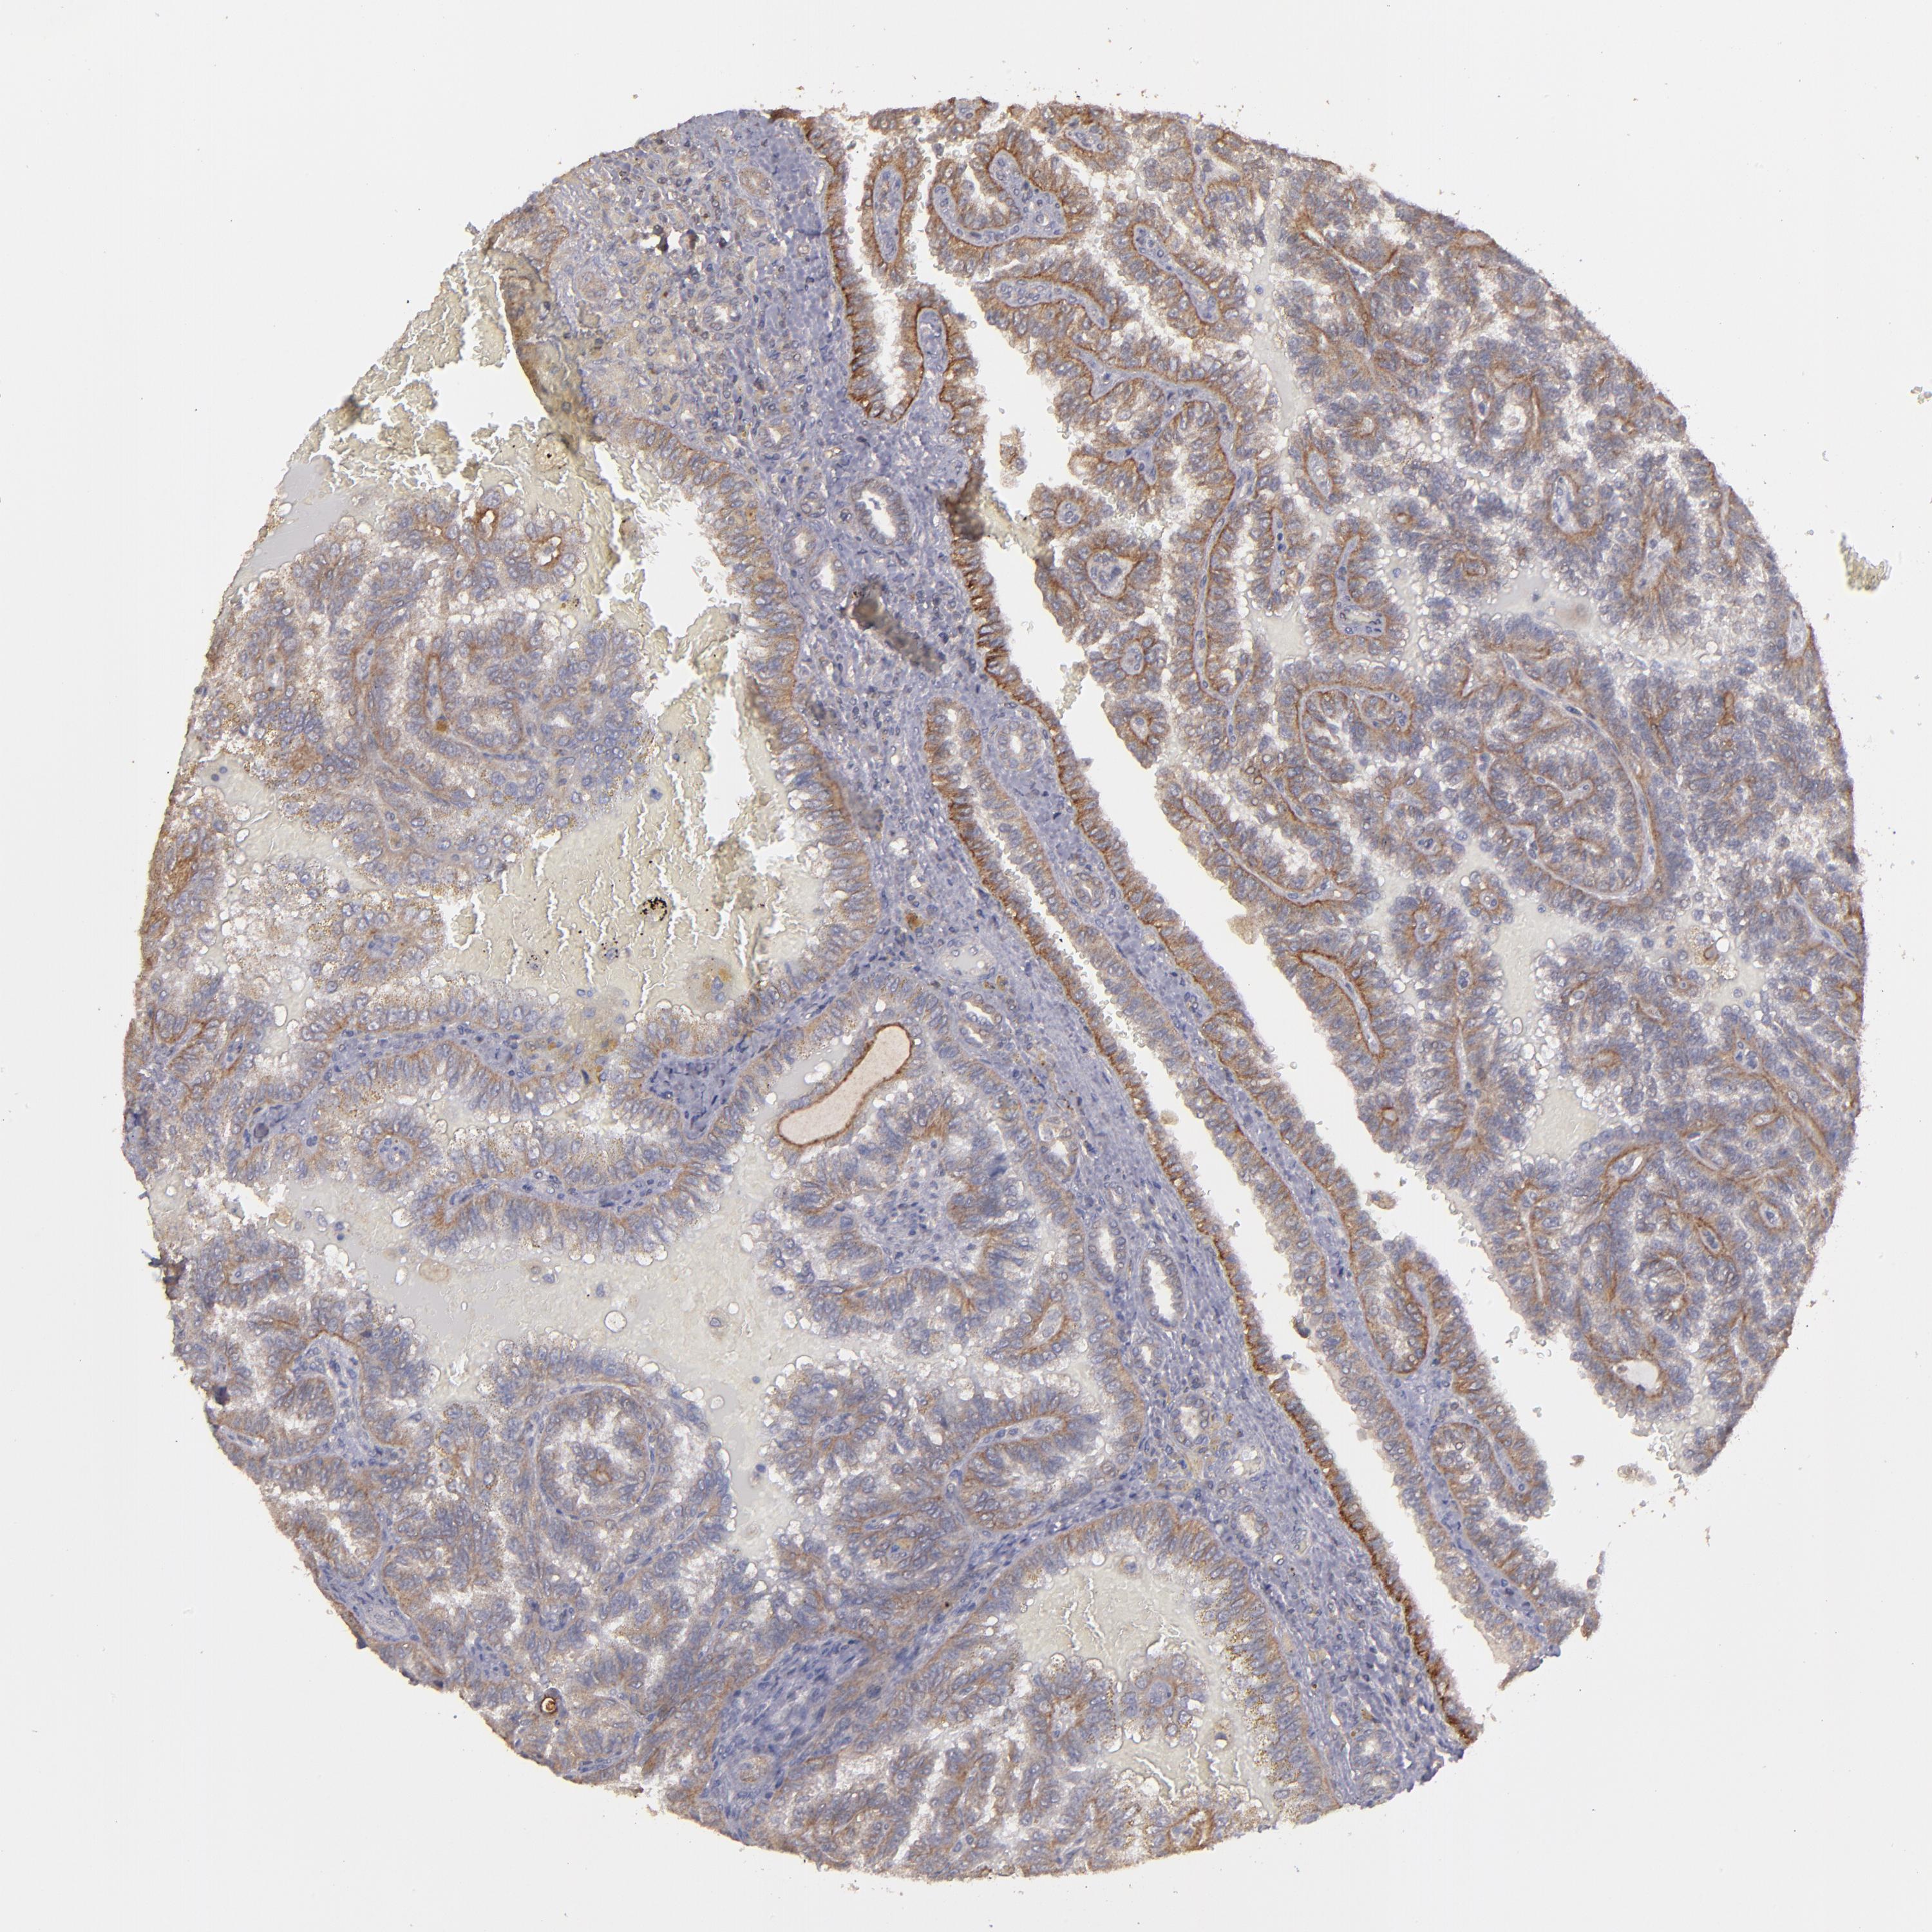

KIDNEY RENAL CLEAR CELL CARCINOMA (VALIDATION) - Interactive survival scatter ploti

The Survival Scatter plot shows the clinical status (i.e. dead or alive) for all individuals in the patient cohort, based on the same data that underlies the corresponding Kaplan-Meier plots. Patients that are alive at last time for follow-up are shown in blue and patients who have died during the study are shown in red.

The x-axis shows the expression levels (FPKM) of the investigated gene in the tumor tissue at the time of diagnosis. The y-axis shows the follow-up time after diagnosis (years). Both axes are complimented with kernel density curves demonstrating the data density over the axes. The top density plot shows the expression levels (FPKM) distribution among dead (red) and alive patients (blue). The right density plot shows the data density of the survived years of dead patients with high and low expression levels respectively, stratified using the cutoff indicated by the vertical dashed line through the Survival Scatter plot. This cutoff is automatically defined based on the FPKM cutoff that minimizes the p-score. The cutoff can be changed by dragging the vertical line or by entering a cutoff value in the square labeled "Current cut-off".

Under the Survival Scatter plot the p-score landscape (black curve; left axis) is shown together with dead median separation (red curve; right axis). Dead median separation is the difference in median mRNA expression between patients who have died with high and low expression, respectively. It is calculated as follows: median FPKM expression of dead patients with high expression - median FPKM expression of dead patients with low expression. This is intended to aid the user in visually exploring custom cutoffs and the associated p-scores and dead median separation.

Individual patient data is displayed and can be filtered by clicking on one or more of the category buttons on the top of the page. Categories describing expression level and patient information include: high, low, alive, dead, female, male and tumor stages. The scale of the x-axis can be toggled between linear and log-scale by clicking on the "x log" button. Mouse-over function shows TCGA ID, patient information and mRNA expression (FPKM) for each patient.

& Survival analysisi

Kaplan-Meier plots summarize results from analysis of correlation between mRNA expression level and patient survival. Patients were divided based on level of expression into one of the two groups "low" (under cut off) or "high" (over cut off). X-axis shows time for survival (years) and y-axis shows the probability of survival, where 1.0 corresponds to 100 percent.

FAT1 is not prognostic in Kidney Renal Clear Cell Carcinoma (validation)

Best expression cut offi

Based on the FPKM value of each gene, patients were classified into two groups and association between prognosis (survival) and gene expression (FPKM) was examined. The best expression cut-off refers the FPKM value that yields maximal difference with regard to survival between the two groups at the lowest log-rank P-value. Best expression cut-off was selected based on survival analysis .

When clicking on this number, the vertical dashed line indicating cut-off, the interactive survival plot, and the Kaplan-Meier curve will be adjusted to show results based on the best expression cut-off.

: 29.47

Average pTPM 47.8

Number of samples 100